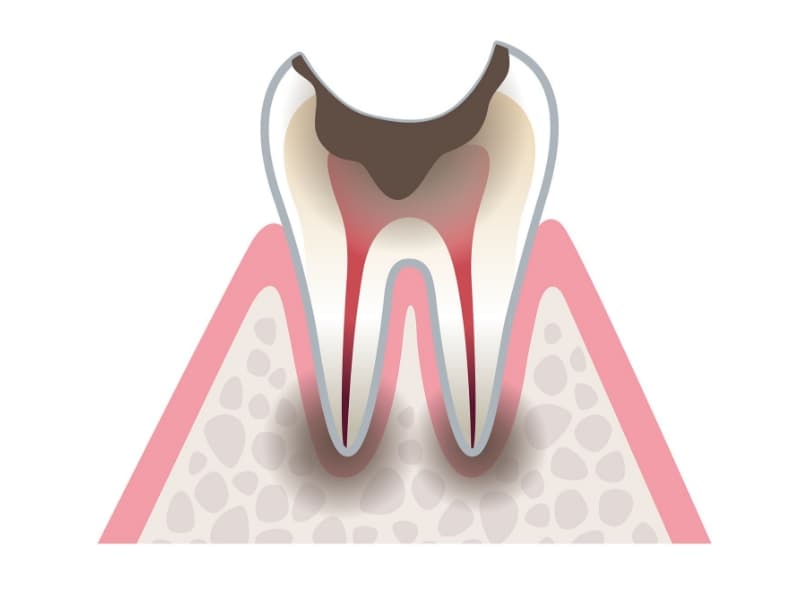

C3神経まで進行したむし歯

炎症が神経にまで及んでいるため、ズキズキと痛みが生じてきます。むし歯を削る量と治療回数が多く、被せ物(クラウン)をする必要が出てきます。